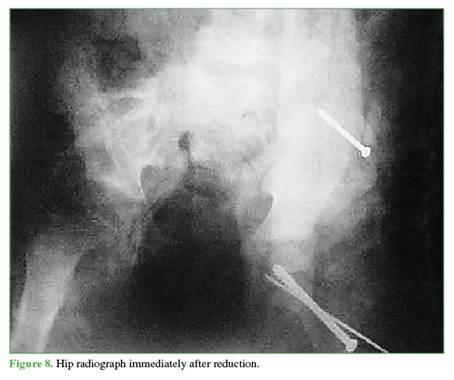

Using the Parsch technique3 via a minimal Hueter approach,4 the displacement of the femoral head was reduced, and a screw and a pin were placed through a minimal lateral approach under fluoroscopic guidance.

Once the hip had been drained and stabilized, another cannulated screw was inserted percutaneously to stabilize the large fragment avulsed from the iliac wing. The patient was immobilized with a hip spica cast to control the open-book component, and soft-tissue traction was applied; the patient was then placed in postoperative traction. Traction was continued for 3 weeks, and anatomical reduction of the fractures was achieved (Figures 6-8).